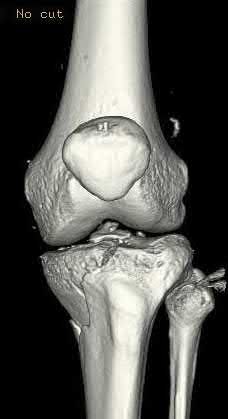

A 38-year-old male suffers the injury shown in Figure A. During operative fixation, free osteoarticular fragments are encountered and reconstruction of these pieces is attempted. Postoperatively, which of the following will have the most beneficial effect on the healing potential of the surviving chondrocytes within these reconstructed articular segments?

Figure A demonstrates a comminuted tibial plateau fracture with significant intra-articular involvement. Basic science evidence has demonstrated that post-operative gentle compressive loading may have a positive impact on articular cartilage healing; however, excessive shear loading may be detrimental.

Irrgang et al provide guidelines for rehabilitation following surgical management of articular cartilage lesions of the knee. They state that after articular cartilage repair, exercises to enhance muscle function must be done in a manner which minimizes shear loading of the joint surfaces in the area of the lesion. The authors also discuss the benefits of gentle compressive loading and motion of the joint, and its positive effects on chondrocyte nutrition.

Furthermore, they recommend a period of protected weight bearing as often being necessary, and that this should be followed by progressive loading of the joint.

Illustration A is a diagram showing the different layers of joint cartilage.